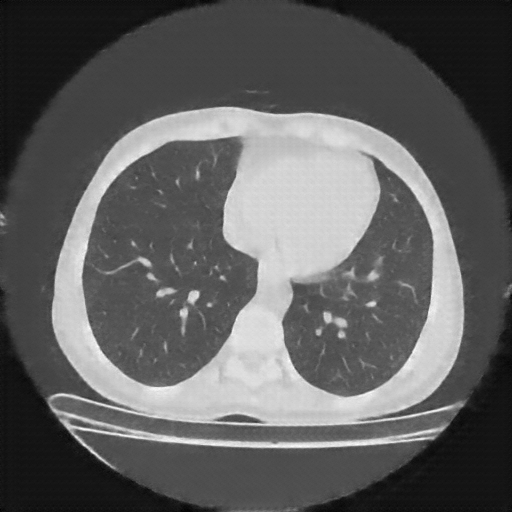

Reconstructed NATIVE CT scan (cycle consistency)

No window - Raw intensity values

Lung window (WL -600, WW 1500 β†’ Low βˆ’1350, High +150)

Mediastinum window (WL 40, WW 400 β†’ Low βˆ’160, High +240)